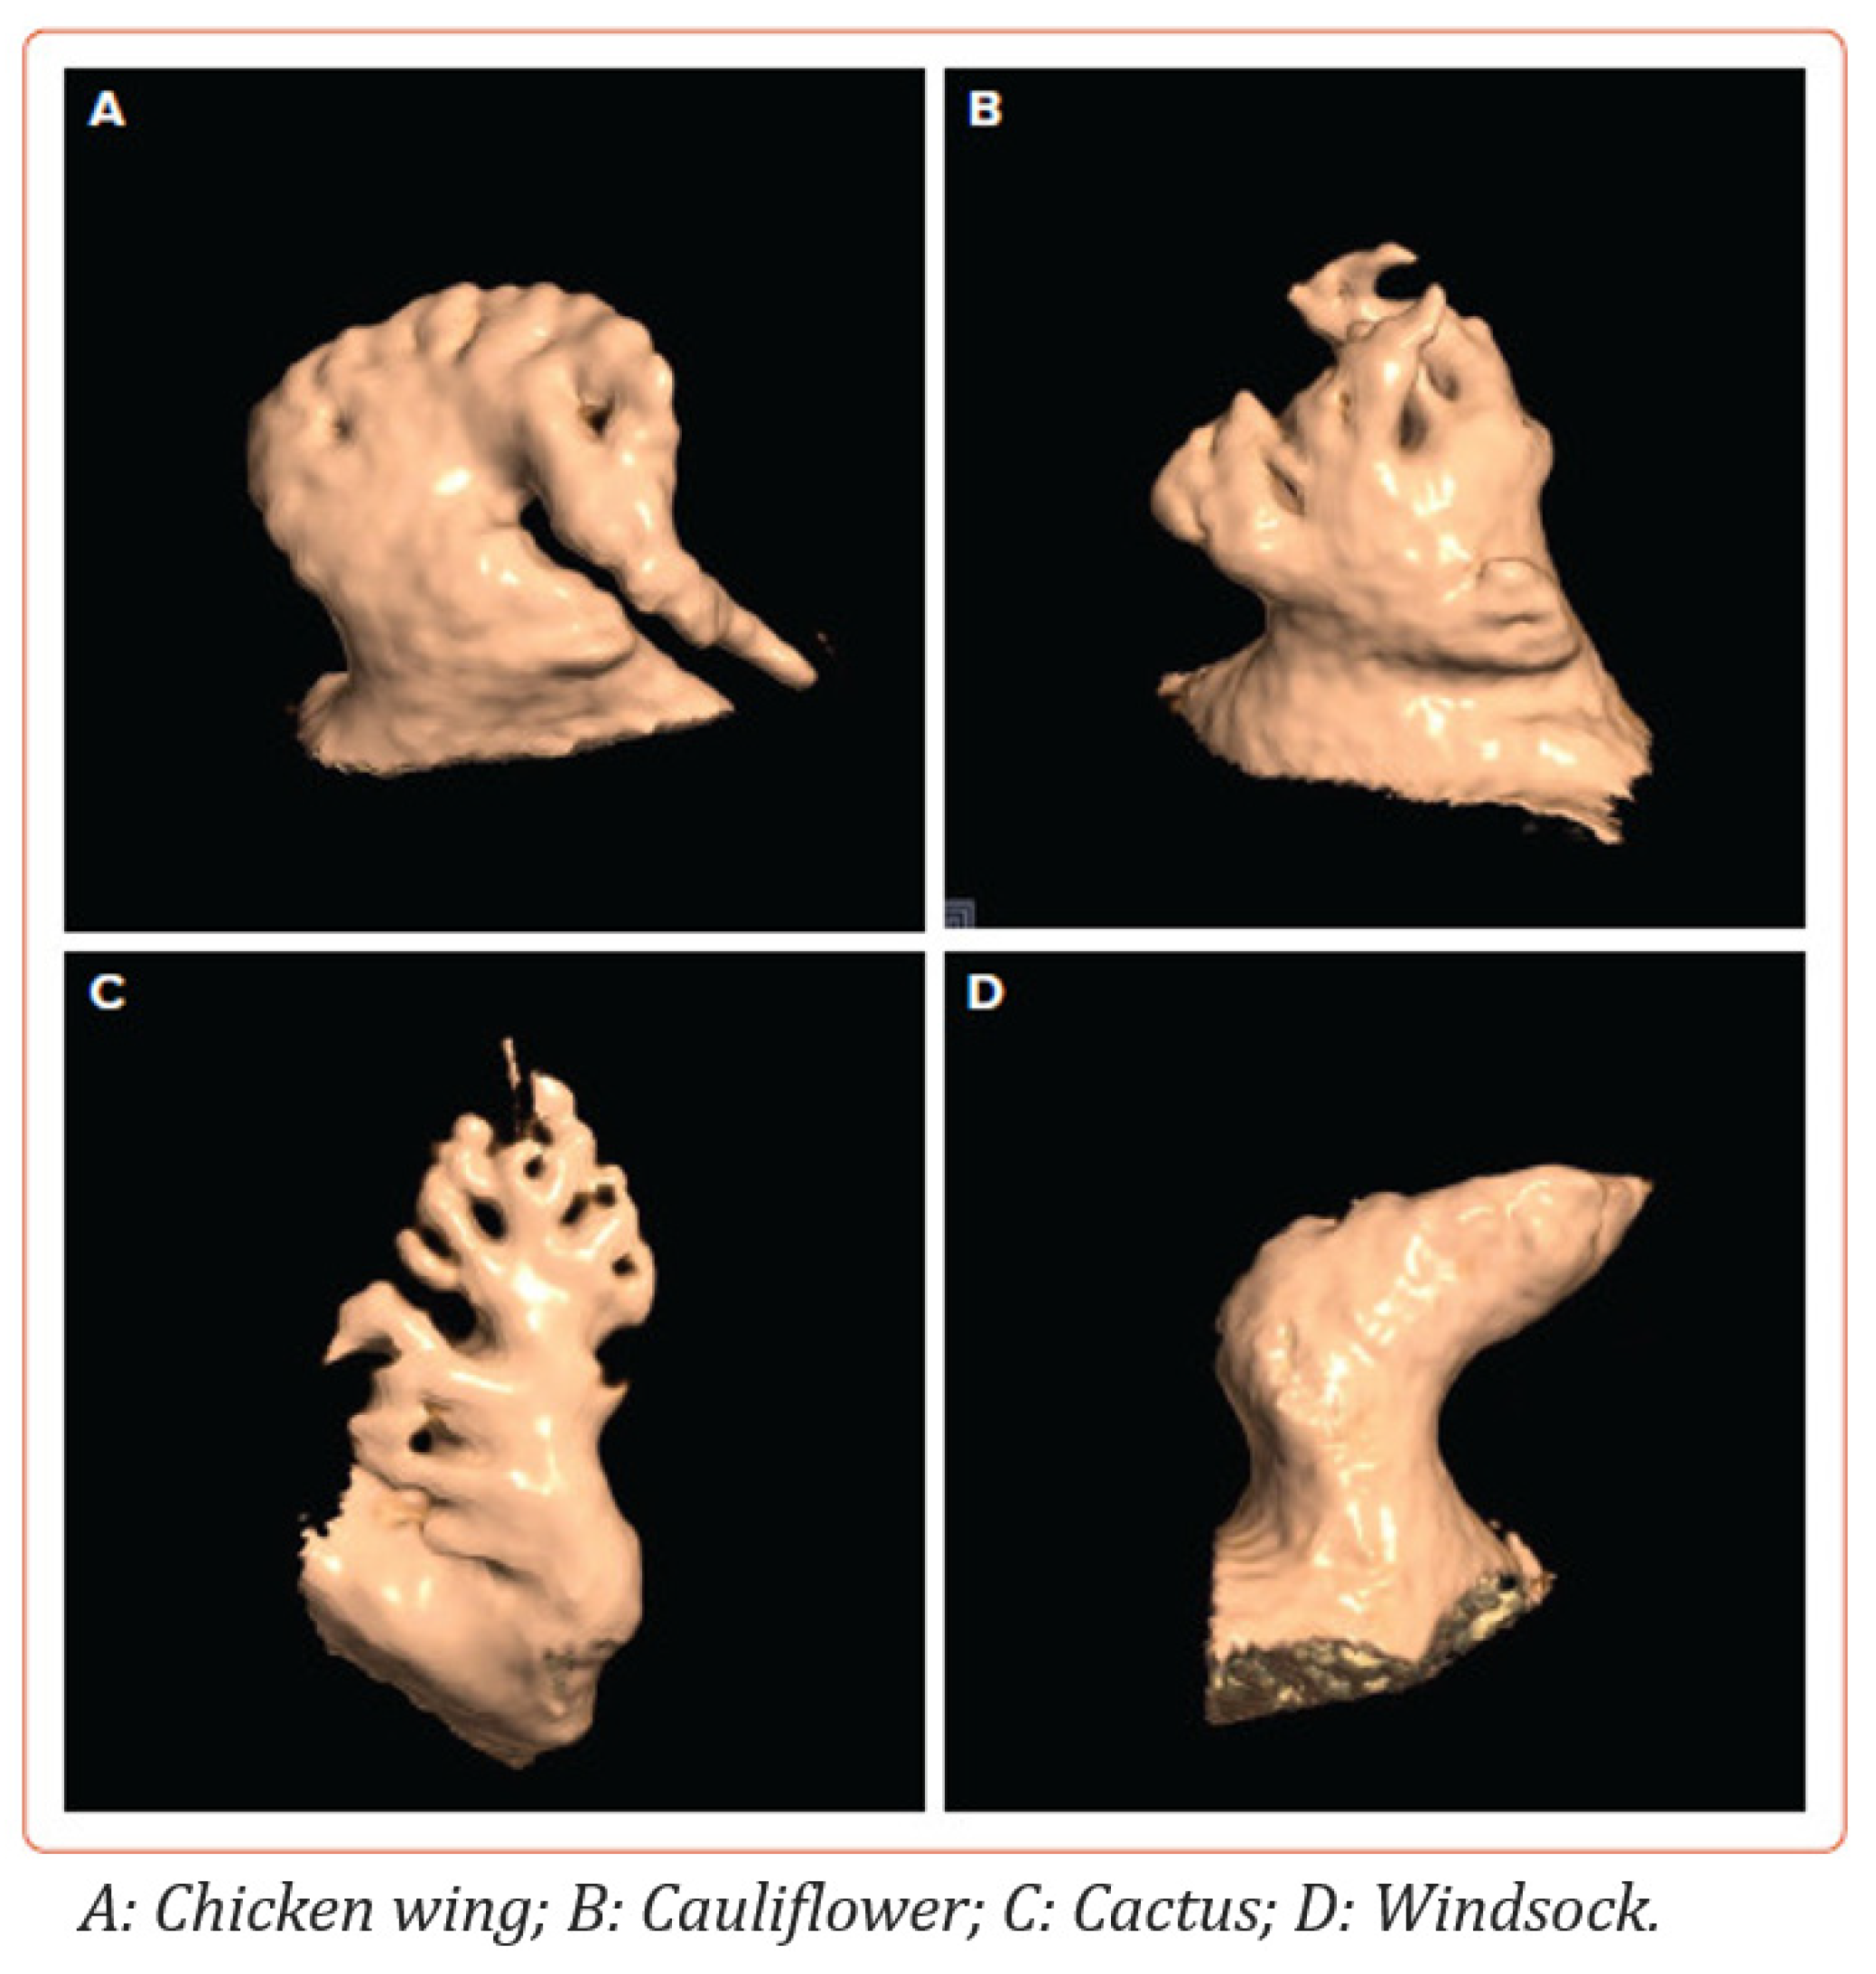

1.3. Left Atrial Appendage Anatomy and Morphology

- Dudzińska-Szczerba, K.; Kułakowski, P.; Michałowska, I.; Baran, J. Association Between Left Atrial Appendage Morphology and Function and the Risk of Ischaemic Stroke in Patients with Atrial Fibrillation. Arrhythm. Electrophysiol. Rev. 2022, 11, e09. [Google Scholar] [CrossRef]

- Lupercio, F.; Carlos Ruiz, J.; Briceno, D.F.; Romero, J.; Villablanca, P.A.; Berardi, C.; Faillace, R.; Krumerman, A.; Fisher, J.D.; Ferrick, K.; et al. Left Atrial Appendage Morphology Assessment for Risk Stratification of Embolic Stroke in Patients with Atrial Fibrillation: A Meta-Analysis. Heart Rhythm. 2016, 13, 1402–1409. [Google Scholar] [CrossRef]

- Di Biase, L.; Santangeli, P.; Anselmino, M.; Mohanty, P.; Salvetti, I.; Gili, S.; Horton, R.; Sanchez, J.E.; Bai, R.; Mohanty, S.; et al. Does the Left Atrial Appendage Morphology Correlate with the Risk of Stroke in Patients with Atrial Fibrillation? Results from a Multicenter Study. J. Am. Coll. Cardiol. 2012, 60, 531–538. [Google Scholar] [CrossRef]